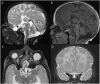

Callosal agenesis is a complex condition with disruption in the steps such as cellular proliferation, migration, axonal growth, guidance, or glial patterning at the midline. Agenesis of the corpus callosum (AgCC) is associated with diverse midline craniofacial malformations affecting the frontal-cranial and midface skeleton. Diagnosing midline abnormalities prenatally can be challenging, especially in twin pregnancies, due to poor resolution of skull base structures on fetal MRI, basal cephalocele could be mistaken for fluid in the nasopharynx, motion limitation, and fetal positioning. Our case highlights the importance of evaluation for other associated midline anomalies when there is callosal agenesis.